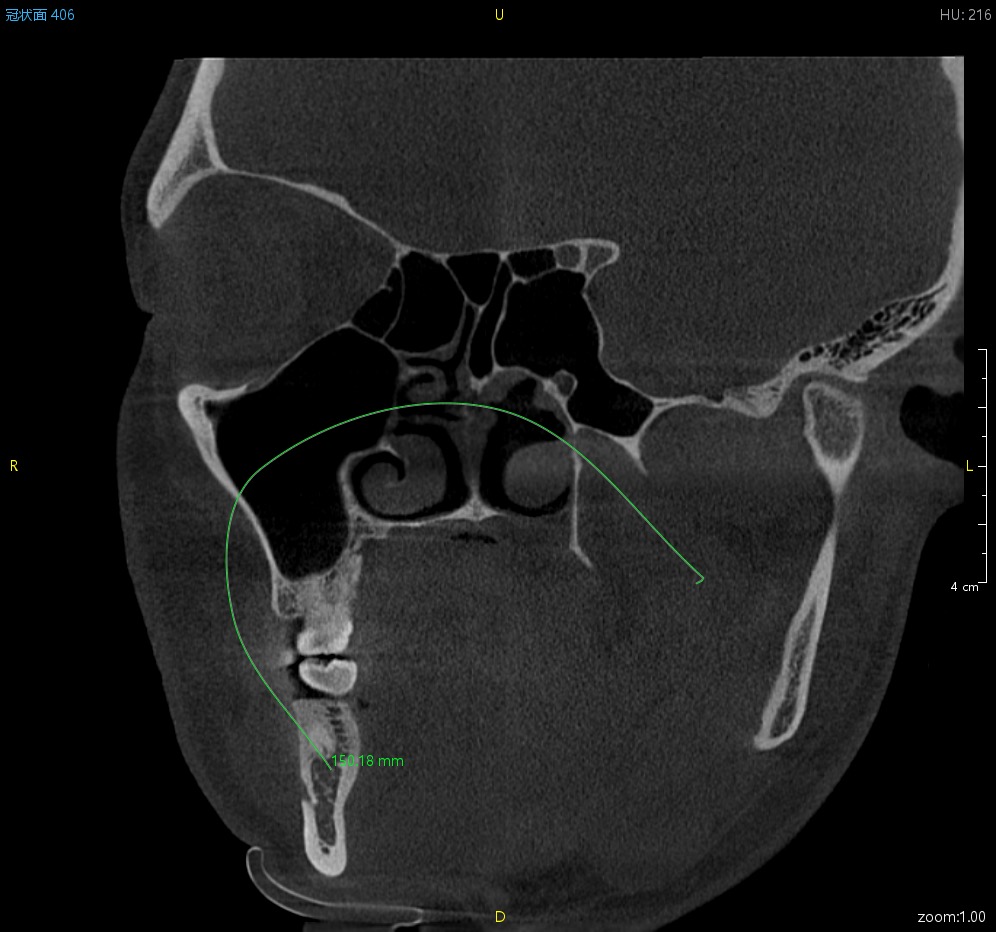

曲线测量

直线测量、曲线测量、折线测量、角度测量、区域面积测量以及骨密度测量

直线测量 折线测量 曲线测量 角度测量 区域测量 骨密度测量 箭头与注释工具